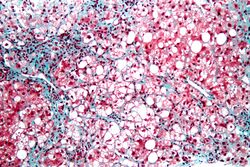

| Micrograph showing a fatty liver (macrovesicular steatosis), as seen in non-alcoholic fatty liver disease. Trichrome stain. |

The fatty change represents the intracytoplasmatic accumulation of triglycerides (neutral fats). At the beginning, the hepatocytes present small fat vacuoles (liposomes) around the nucleus (microvesicular fatty change). In this stage, liver cells are filled with multiple fat droplets that do not displace the centrally located nucleus. In the late stages, the size of the vacuoles increases, pushing the nucleus to the periphery of the cell, giving a characteristic signet ring appearance (macrovesicular fatty change). These vesicles are well-delineated and optically "empty" because fats dissolve during tissue processing. Large vacuoles may coalesce and produce fatty cysts, which are irreversible lesions. Macrovesicular steatosis is the most common form and is typically associated with alcohol, diabetes, obesity, and corticosteroids. Acute fatty liver of pregnancy and Reye's syndrome are examples of severe liver disease caused by microvesicular fatty change.[19] The diagnosis of steatosis is made when fat in the liver exceeds 5–10% by weight.[13][20][21]